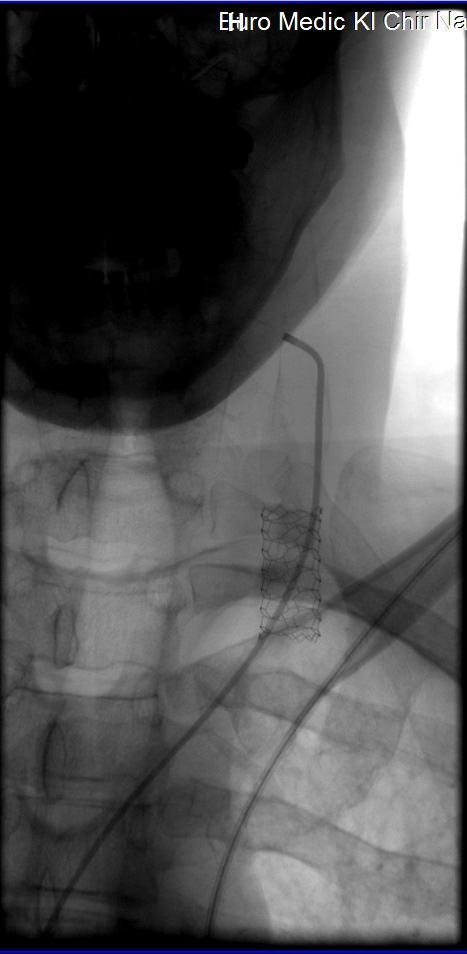

Geen Doppler? Nee, al mijn adertjes waren prima in orde......op 1 klep na die volledig dicht zat. Dus reflux van bloed. Tijdens operatie kon goed gezien worden dat voor de rest het bloed goed stroomde. De klep werd open'gedotterd' (kapot gemaakt dus), maar daarna klapte de ader dicht

Dus werd mij gevraagd of ik een stent wilde van 3cm. De doc vertelde dat sommige patienten geen stent wilde. Ik heb gevraagd wat de risico's waren , of de stent veilig was. De doc zei dat niet zoveel stents plaatsten maar dat het niet risicovol was. Tsja, dan lig je daar....Dus voor mezelf de afweging gemaakt; geen stent betekent geen oplossing, de plaats voor de stent lijkt veilig (achter mijn sleutelbeen, vertikaal). Dus ik heb geantwoord dat de stent er in moest! Nou, dan volgt er wat gewroet en je voelt precies waar wat gebeurt, en dan zit de stent.

Overigens voelde en hoorde ik wel tijdens het dotteren gekraak en geplop naast mijn linkeroor, was waarschijnlijk de klep.

Na een paar uur kwam er een assistent-dokter die met de Doppler de bloedstroom controlleerde en die was goed. Hij heeft ook nog even naar de stent gezocht, maar kreeg die niet in beeld (zit ook grotendeels achter een bot)

stent.jpg

stent.jpg [ 73.05 KiB | 100903 keer bekeken ]